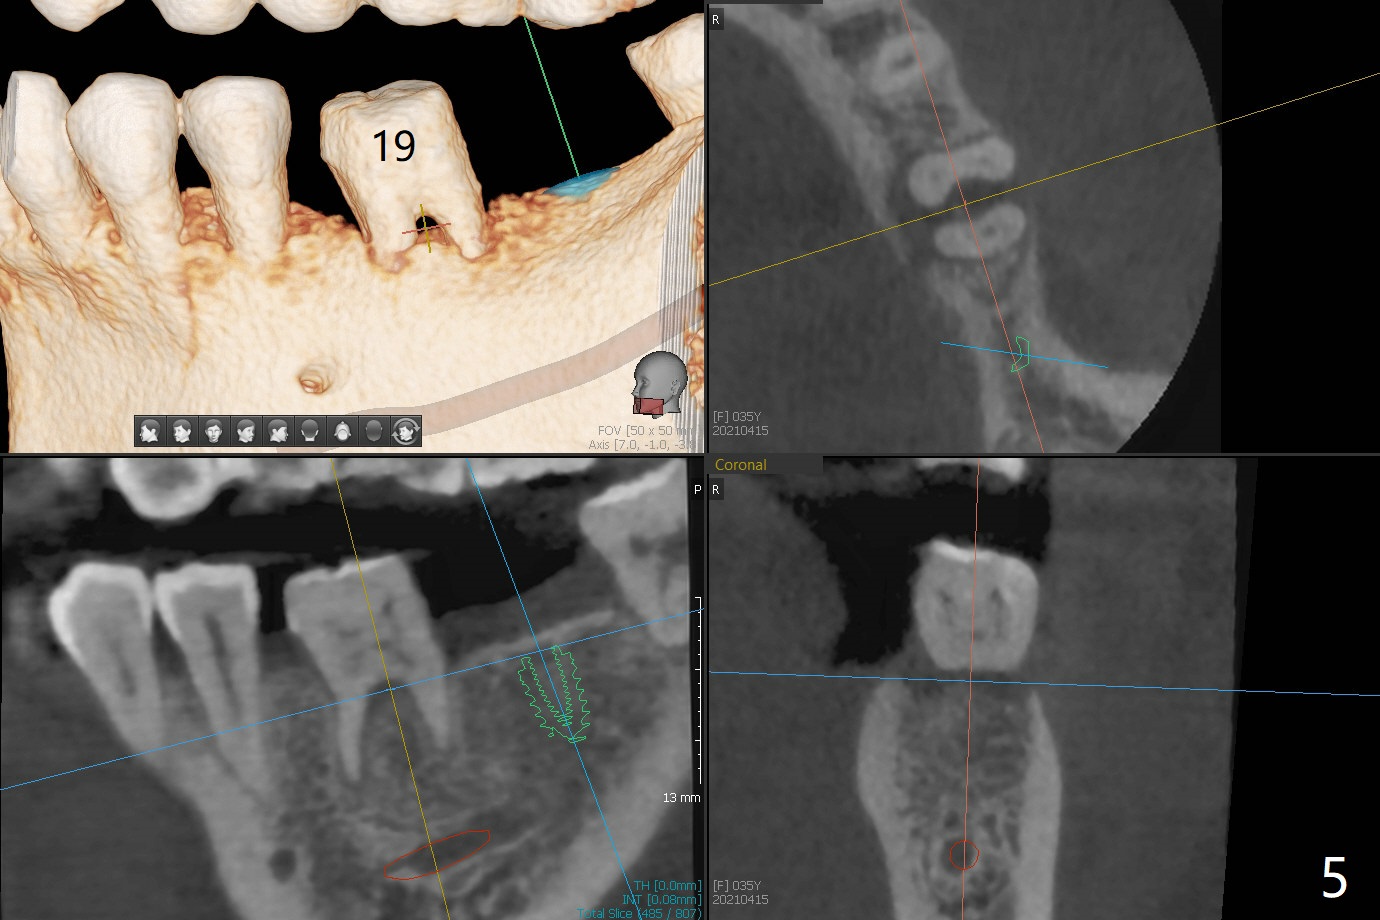

A 35-year-old woman has had guide

Xin Wei, DDS, PhD, MS 1st edition 04/15/2021, last revision 05/14/2021